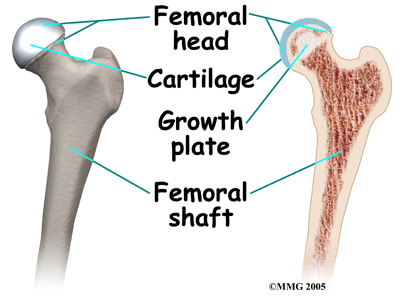

The hip is a ball-and-socket joint. A tough lining called the synovium covers it. The ball of the joint is the end of the thigh bone, called the femur. Like other ends of bones in children, the ball has an area called a growth plate. A growth plate has cells that produce new bone. The growth plate is weaker than other parts of the bone. This makes this area more likely to fracture.

The socket part of the hip joint is called the acetabulum. It is actually part of the pelvis. The acetabulum forms a cup where the ball of the femur sits. It is covered with articular cartilage. Articular cartilage is the material that covers the ends of the bone of any joint. It's a rubbery, slippery substance that allows the surfaces to slide against one another without damage to either surface.